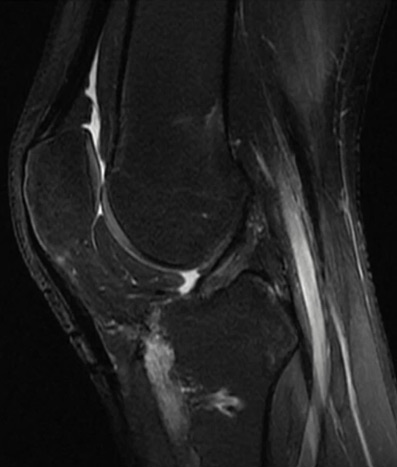

Pre operative MRI

- Knee MRI Findings:

- Rupture of the PCL, PLC and LCL

- Intact ACL

- No meniscal tear

- No cartilage injury